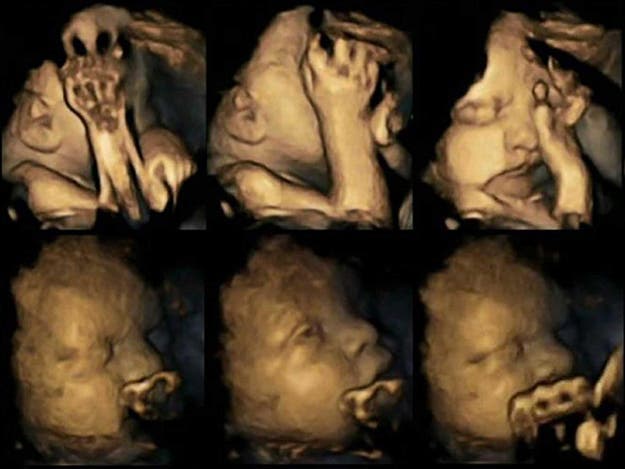

Dans le cadre d’une recherche sur les effets du tabagisme sur les fœtus, certains chercheurs de l’Université de Durham ont réalisé des échographies en 4-D montrant les bébés à naître de femmes fumeuses d’un côté, et des fœtus portés par des femmes non fumeuses de l’autre. Les résultats sont réellement effroyables :

Les chercheurs se sont essentiellement concentrés sur les mouvements de la main et de la bouche observés chez tous les fœtus, qu’ils soient de mamans fumeuses ou de mamans non fumeuses. Quatre des vingt grossesses étudiées par ces chercheurs concernaient des mamans fumeuses, et des échographies ont été réalisées sur chaque femme entre sa 24ème et sa 36ème semaine de grossesse.

Les chercheurs ont découvert avec effroi que les fœtus portés par les mamans fumeuses avaient tendance à se toucher le visage et la bouche beaucoup plus souvent que les fœtus de mamans non fumeuses.

Les fœtus portés par les mamans fumeuses présentaient une augmentation de 58% des mouvements de la bouche et une augmentation de 69% du toucher de soi.

Cette hausse considérable de mouvement pourrait indiquer que la nicotine et autres toxines contenues dans les cigarettes ont des effets néfastes sur le développement du fœtus qui semble essayer de se protéger de quelque chose.